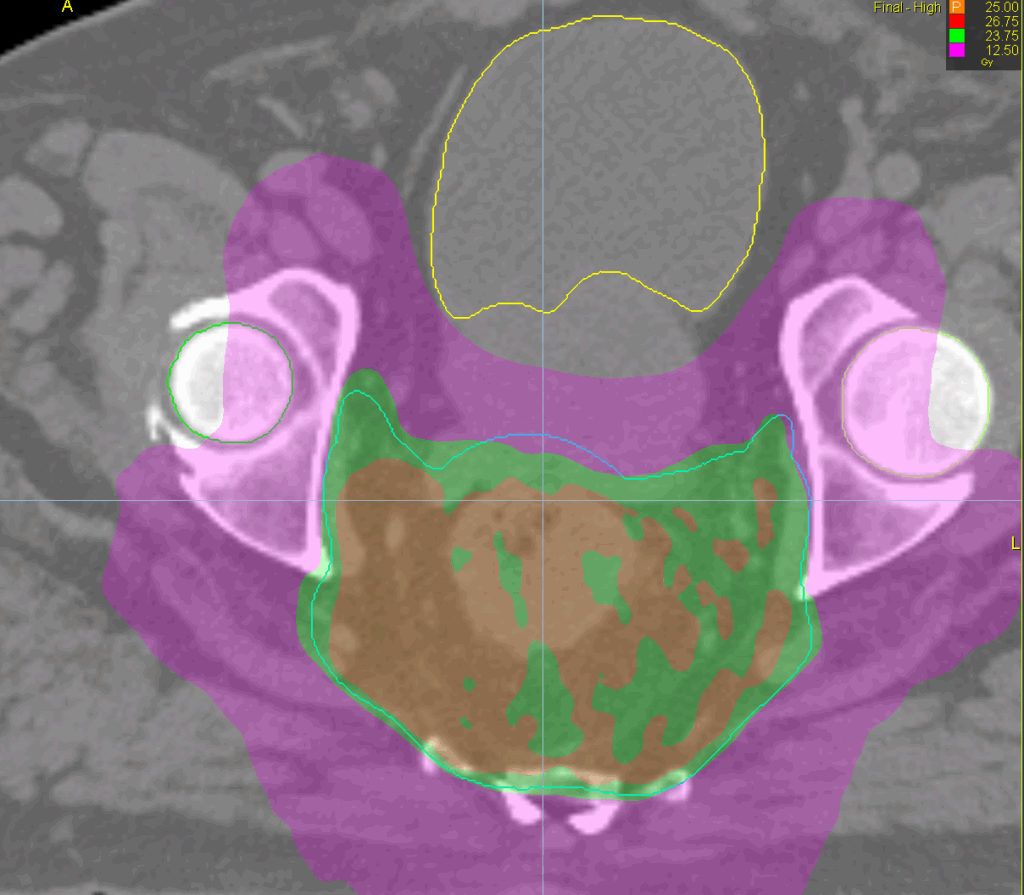

Treatment Plan Images

PTV(s) Volume, Length

1050 cc, 12 cm

TomoHelical™ 5cm